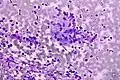

Micrograph of a Field stain showing malignant melanoma.